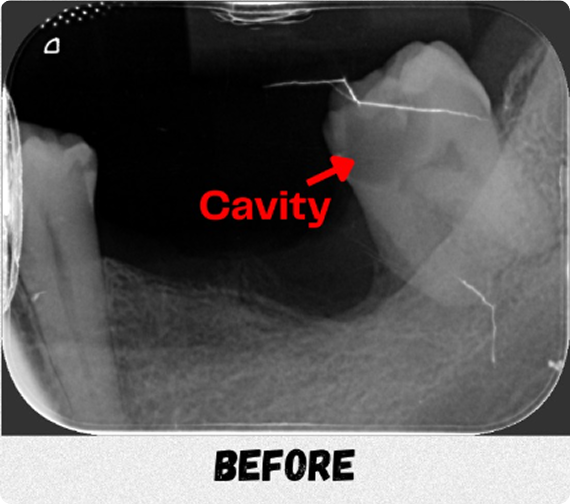

“Instead of extraction, I chose root canal therapy because it’s the only molar he has left on this side to chew.”- Dr Karen